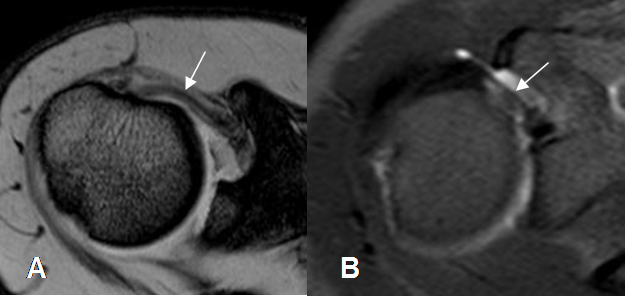

El intervalo rotador es mejor evaluado con las secuencias sagitales. La presencia de líquido en esta región es el principal signo de patología. (9). (Fig 30 y 31).

Fig 31. Intervalo anormal.

A y B: RM sagital en STIR. Presencia de líquido y cambios inflamatorios en el intervalo rotador, como hallazgo patológico.